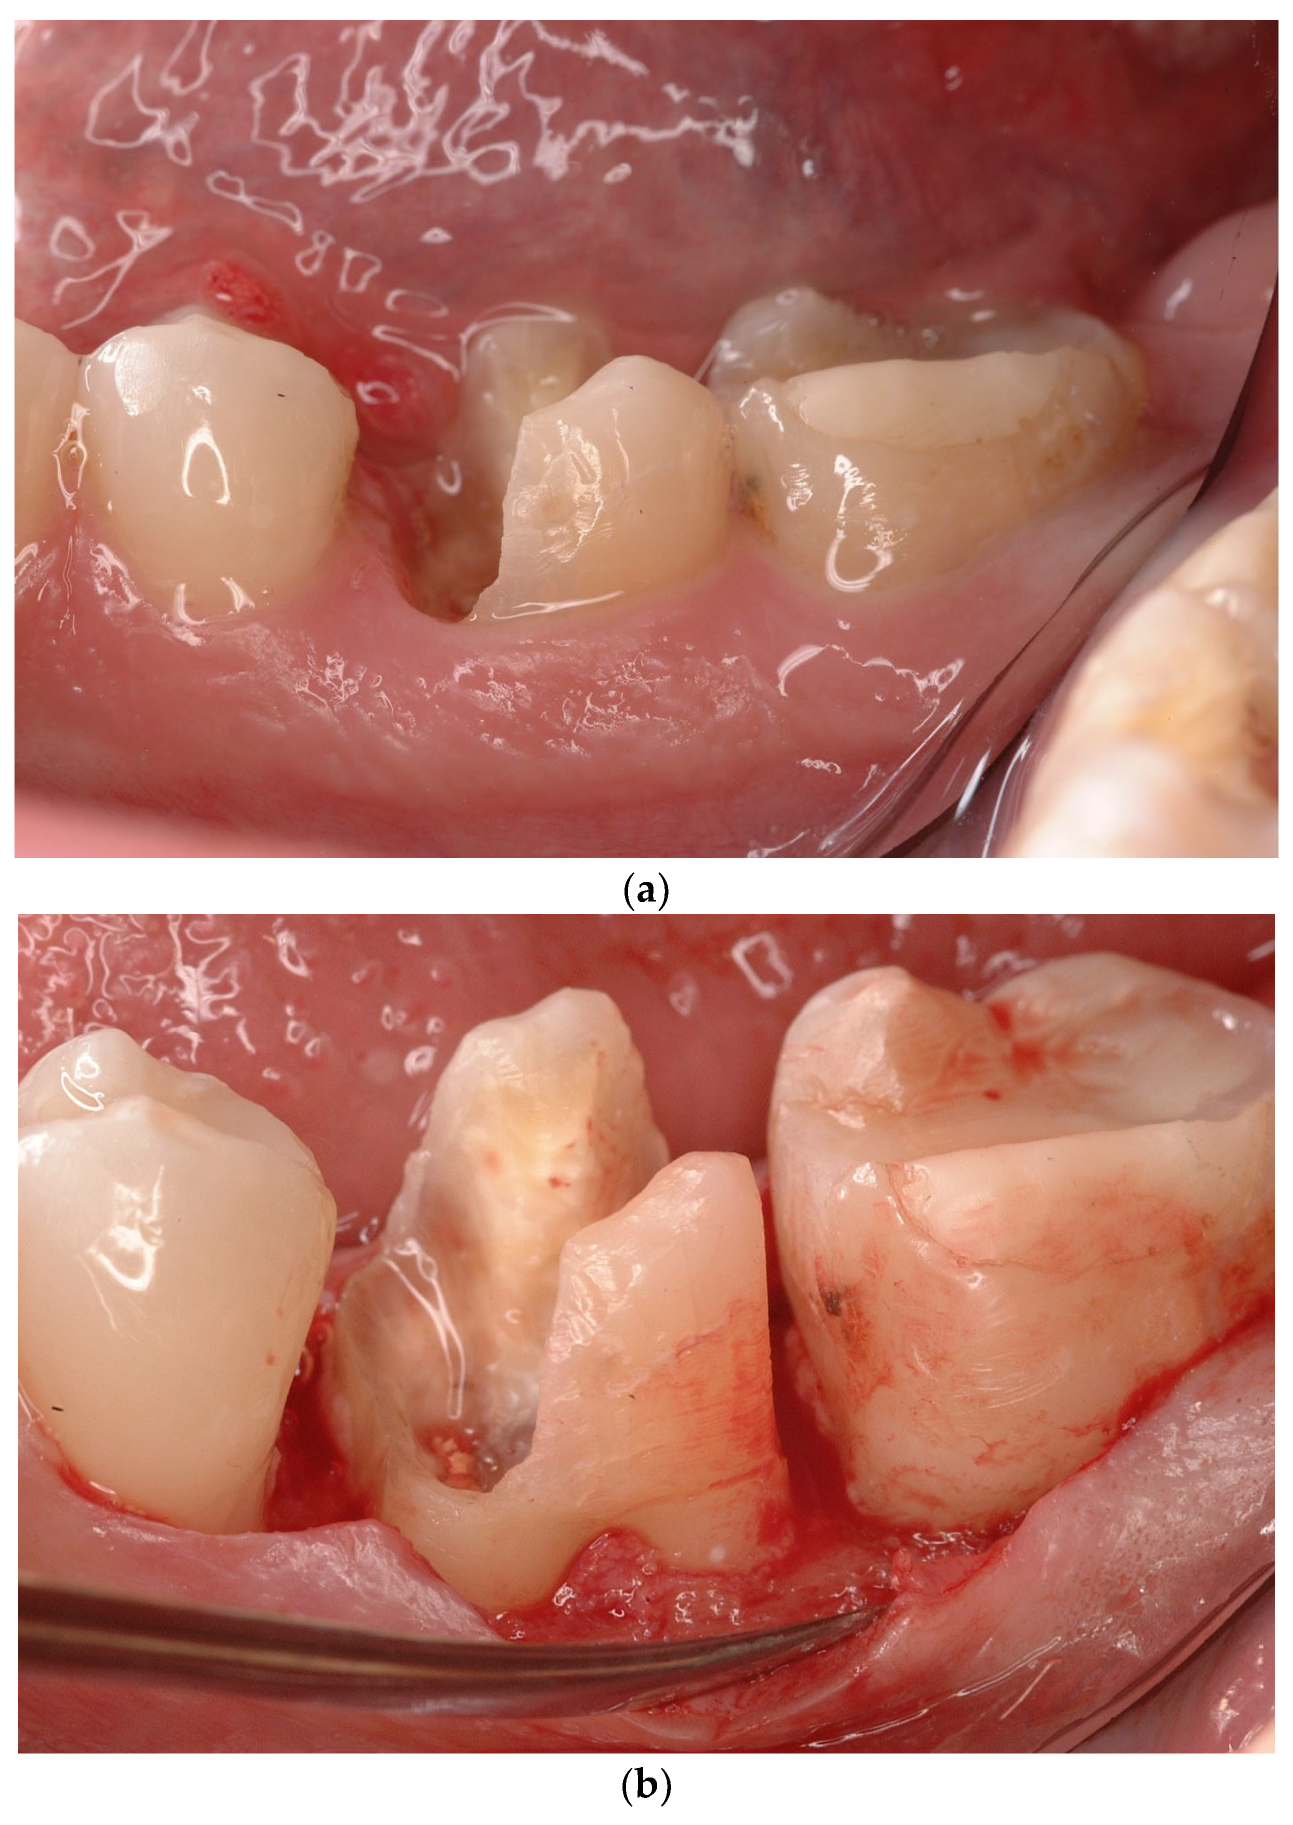

- 3.

- Subcrestal Attachment Level fracture (SAL)

4.5. Treatment

- A. Subcrestal Attachment Level fracture (SAL)—cervical third.

- Treatment options #2: Extraction and replacement with implant therapy or adhesive restoration

- B. Subcrestal Attachment Level fracture (SAL)—middle third